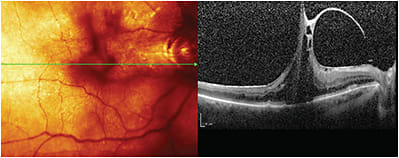

Left eye with severe vitreomacular traction syndrome.

IMAGE COURTESY STEVEN G. SAFRAN, MD